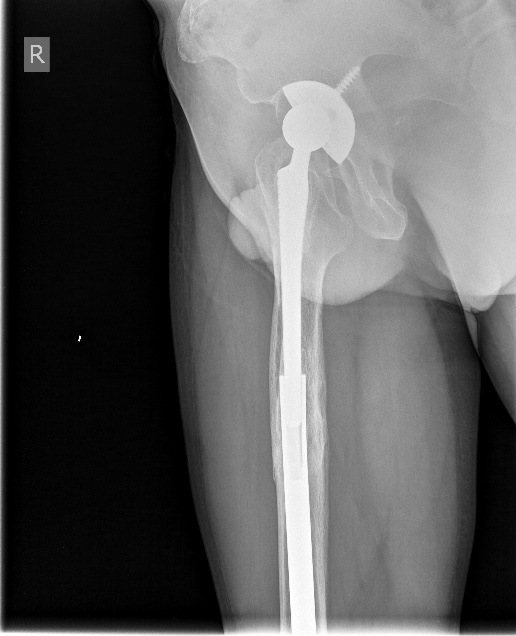

[Ortho] Перимплантный перелом бедра

Закрытое штифтование с удлинением бесцементной ножки при переломах

Vancouver B2/ B3 дает неожиданно для приверженцев традиционной догмы

хорошие результаты.

Здесь  - http://weborto.net/forum/1256380983/ -  первое наше наблюдение

такого остеосинтеза с нестабильной ножкой. Прошло уже 6 лет - вот

недавние снимки. Пациент не имеет жалоб, катается на коньках. Никакие

дистальные винты не выдержали бы циклических нагрузок столько лет, если

бы ножка оставалась нестабильной.